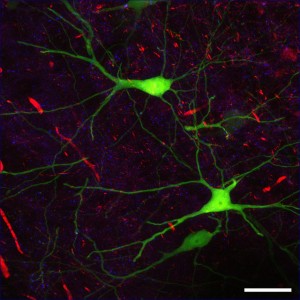

Elevated levels of B2M have been found in patients with cognitive disorders associated with aging and even those with Alzheimer’s. First, Villeda’s team measured the protein in the blood of mice and people of varying ages and confirmed that the levels are increased with age. Then researchers injected the protein into three-month-old mice and discovered that these mice were having issues with memory loss. They struggled to complete a water maze, the mice made more than twice the mistakes after they had been trained to get through the maze. This occurred because these mice had less new neurons than other young mice. Villeda believes that this ongoing research proves that the blood can be manipulated instead of the brain in an effort to treat memory impairment. This is a much easier endeavor when thinking of human patients. This could mean that removing the protein B2M would save cognitive memory loss.

Villeda is a former postdoc in the Wyss-Coray lab. As a professor, Villeda had a desire to study blood factors that are implicated in previous studies that contribute to aging, such as B2M in the hopes of reversing the memory loss or saving thoughts of years past by removing the protein. It has been well-known by scientists that B2M has a role in pruning nerve cell connections in young, developing brains.

Third Photo Courtesy of ZEISS Microscopy of Flickr Page – Creative Commons License